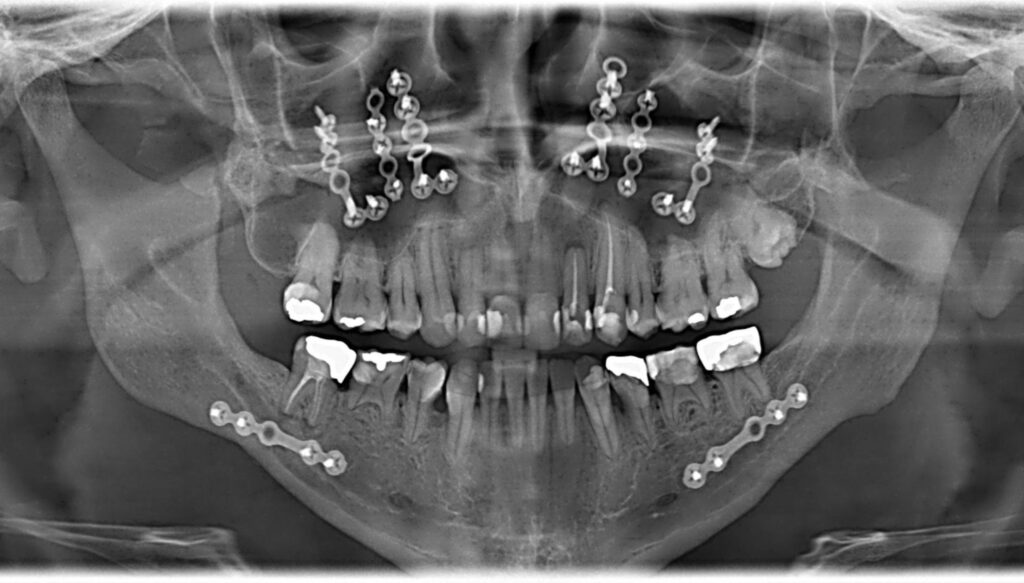

Restore function, comfort, and confidence with precision oral surgery in our modern clinic. At Dynasty Stomatology, we offer a comprehensive range of surgical procedures — from routine tooth extractions and wisdom tooth removal to complex jaw reconstruction, bone grafts, and oral maxillofacial surgery. All diagnostics, planning, and care take place on-site — saving you time and ensuring continuity at every stage of treatment.

At Dynasty Stomatology, every essential step — from high-resolution diagnostics (CT, tomography, dental X-rays) to guided bone regeneration, sinus lift, and prosthetic restoration — happens right here. No referrals, no additional travel. Your oral surgery is planned and delivered by one team under one roof, with every detail tailored to your condition and general health.

Whether it’s alveolar bone surgery, impacted teeth removal, or dental implant surgery, we take time to plan your treatment properly. With the use of proven materials, local anesthesia, and techniques supported by research, we minimize stress and pain. Even major dental procedures are performed in a safe, calm environment — built around your comfort.

Our surgeons use digital planning, modern surgical protocols, and certified materials (including titanium abutments, bone tissue grafts, and artificial tooth roots) to ensure high precision, safe healing, and successful osseointegration. You’ll receive consistent post-surgical care and clear instructions — from the first visit to full recovery.

Oral surgery is a specialized area of dentistry dedicated to diagnosing and treating defects, injuries, and diseases of the mouth, jaw, and facial regions. It encompasses far more than simple removals; it involves complex surgical procedures that are essential for restoring the ability to chew, preparing the mouth for prosthetic work (like implants), and correcting congenital or trauma-related anomalies of the jawbone.

At Dynasty Stomatology, we ensure a comprehensive treatment plan for every patient. This ranges from eliminating deep infections via oral cyst removal to using a specialized bone graft or sinus lift to reverse bone loss and establish a strong foundation for a permanent artificial tooth root. Every procedure is performed with minimal invasiveness under controlled anesthesia, prioritizing a fast and smooth healing process.

The oral surgeon conducts a thorough examination, including 3D Tomography (CT), to assess your bone tissue volume and pinpoint the exact area requiring intervention.